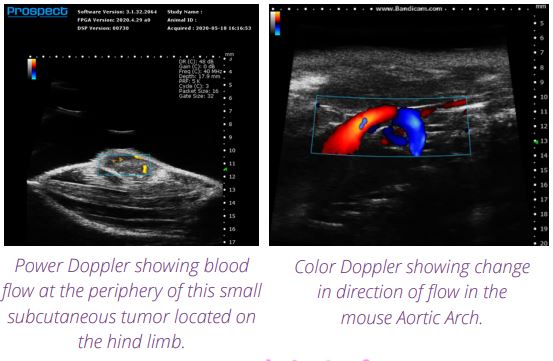

小动物超声成像系统Prospect T1配备了标准超声功能,包括B模式、EKV模式、M模式、彩色和功率多普勒、脉冲波多普勒、组织多普勒和对比成像(可选择参考减法和谐波)。此外,该系统的功能可以通过添加3D电机来获取3D B模式图像、集成超声波穿孔探头以与微气泡一起使用、或推动探头以执行剪切波弹性成像来扩展,*后,集成注射支架也可以用于辅助图像引导注射。